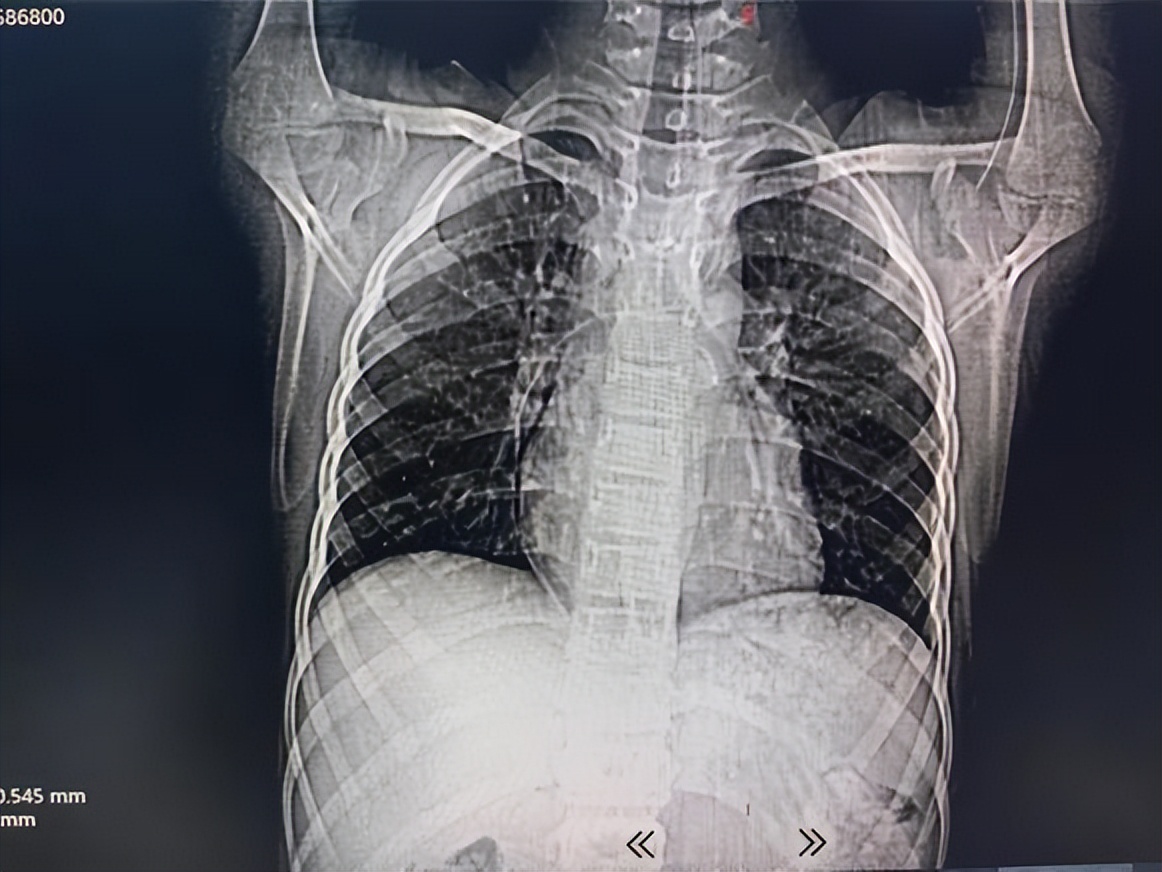

术前CT及胸片显示腋静脉段导管(箭头示)弯折断裂。

虽然宝宝无特殊不适,但考虑到心室内异物可能会引起心律失常、血管损伤,甚至于严重者会出现心脏骤停等风险,血液科紧急请介入血管瘤科会诊,在进一步完善一些检查以后发现导管漂移至肺动脉远端,近端位于肺动脉干及右心室间。

随后复查CT及三维重建显示:导管断裂,远端漂移至右下肺动脉。